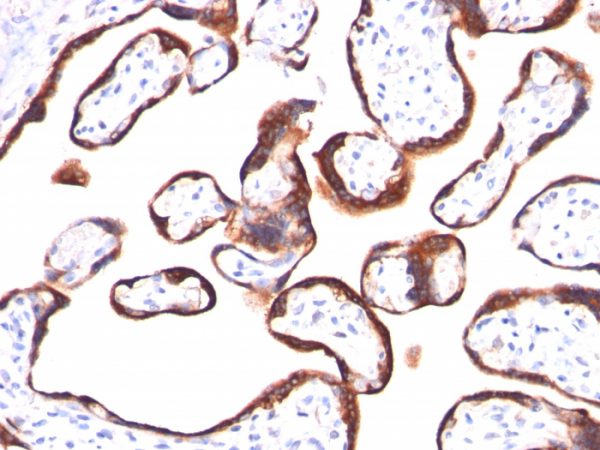

HCG-beta (Pregnancy & Choriocarcinoma Marker) Antibody [HCGb/459]

This MAb reacts with a protein of 22kDa, identified as beta sub-unit of HCG. It does not cross react with the alpha sub-unit. HCG is a glycoprotein, which is secreted in large quantities by normal trophoblasts. It is present only in trace amounts in non-pregnant urine and sera but rises sharply during pregnancy. HCG is composed of two non-identical, non-covalently linked polypeptide chains designated as the subunit is identical to that of thyroid stimulating hormone (TSH) follicle stimulating hormone (FSH), and luteinizing hormone (LH). HCG MAb detects cells and tumors of trophoblastic origin such as choriocarcinoma. Large cell carcinoma and adenocarcinoma of the lung demonstrate anti-hCG positivity in 90% and 60% of cases respectively. 20% of lung squamous cell carcinomas are positive. HCG expression by non-trophoblastic tumors may indicate aggressive behavior.

JAR or TT cells. Placenta.